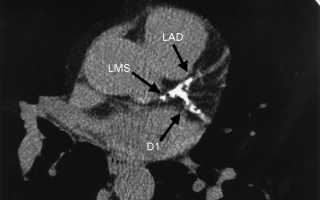

Кальциевый индекс коронарных артерий определяют на мультиспиральном томографе.

Индекс кальцификации коронарных артерий показывает насколько опасной является масса отложений в аортокоронарных сосудах.

Диагностика на томографе занимает не более десяти минут. Бляшки видны, как пятна белого цвета.